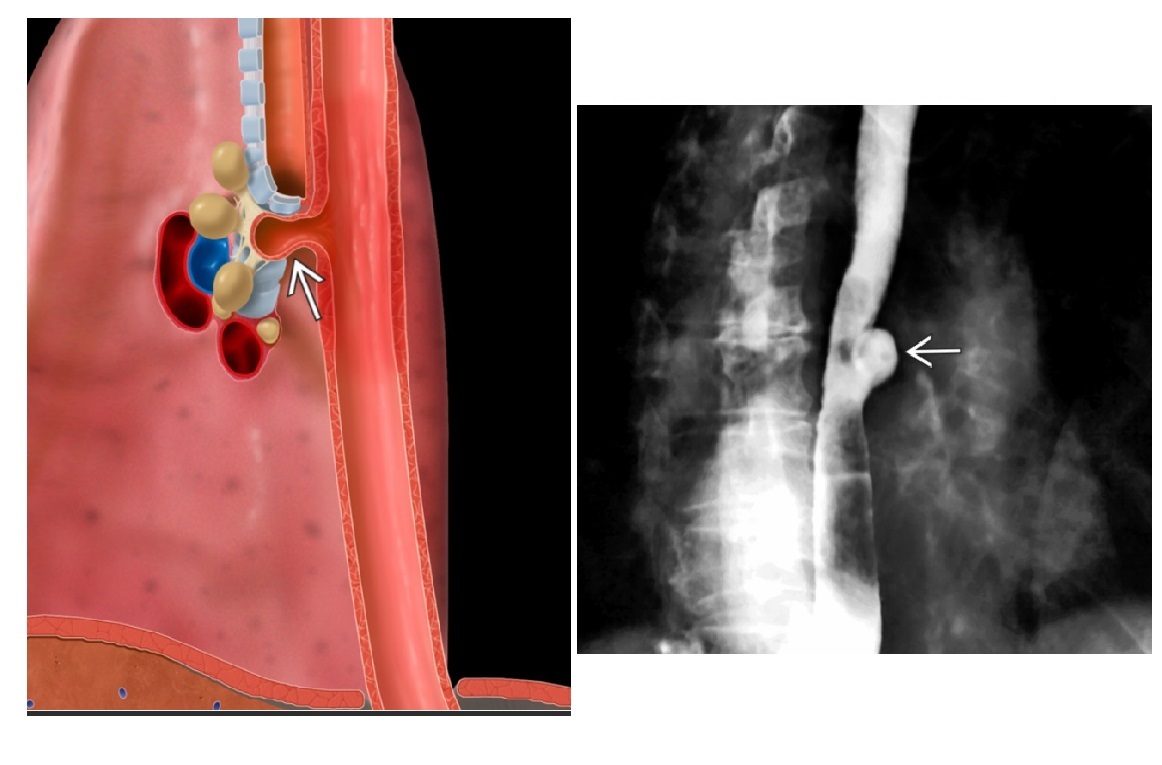

Zenker Diverticulum

In hypopharynx!!!

Site of weakness is the Killian dehiscence - between the inferior pharyngeal constrictor muscle and cricopharyngeal muscle

Dysphagia in elderly person. Previous TB. Barium-filled tented or triangular outpouching in the mid oesophagus ?

A

Traction diverticulum

Acquired condition due to subcarinal or perihilar granulomatous lymph node pathology (TB, histo)

External force on oesophageal wall, such as mediastinal inflammation, that adheres and pulls on oesophageal wall